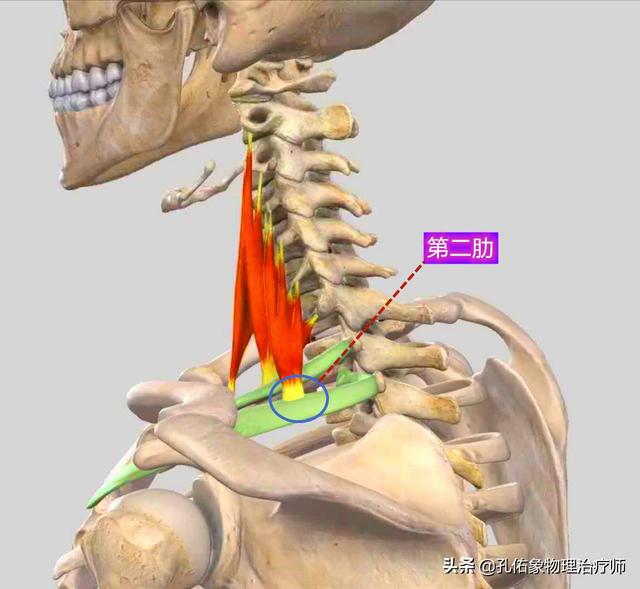

2) Deuxième raison : bien que rares, lesFacilement mal diagnostiquéC'est le problème des releveurs de l'omoplate décrit plus haut. Une autre structure importante est le muscle oblique postérieur, comme indiqué ci-dessous :

Ce muscle, l'oblique postérieur, se développe à une extrémité sur les vertèbres cervicales 6 et 7 et sur l'apophyse transverse.L'autre extrémité se trouve sur la deuxième nervure du côté arrière.(b) Si elle est due au fait qu'elle est souventEn baissant la tête, ce muscle se raccourcit et se tend, ce qui provoque une douleur au niveau de la cage thoracique.. Ici, bien qu'elle ne soit pas attachée à l'omoplate, dans une large mesure, la douleur dans cette position n'est pas un très petit point de douleur confiné, le point de douleur de l'omoplate.Il s'agit souvent d'un domaine qui fait l'objet d'un diagnostic erroné.La figure ci-dessous présente les éléments suivants :

Avec une telle zone de douleur, il est probable qu'il s'agisse d'un problème au niveau du muscle oblique postérieur, facilement confondu avec un problème au niveau du muscle releveur de l'omoplate.La douleur provoquée par le muscle oblique postérieur est plus profonde et plus supérieure.。